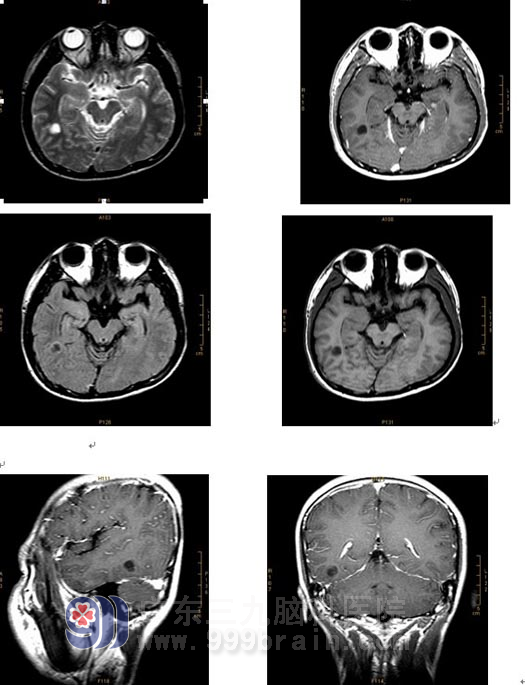

影像学(磁共振)表现:

右侧颞叶示一孤立性类圆形长T1、长T2异常信号影,FLAIR序列呈低信号影,周边伴有环形高信号影,病变边界清晰,周围未见脑组织水肿,占位效应不明显,增强后,病变未见异常强化。与外院前片(2007-5-7MRI)对比,病变大小及信号大致同前。诊断:右颞叶病变,考虑胚胎发育不良性神经上皮瘤。